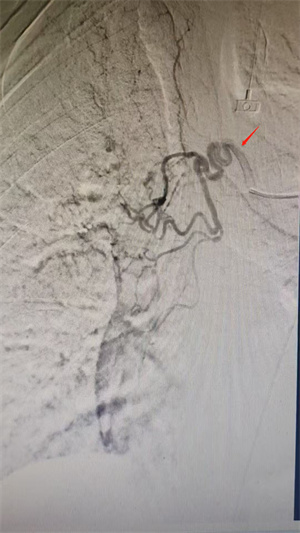

患者高龄,脉氧偏低,且支气管动脉变异较多,术中超选困难,无疑增加了手术时间,手术难度较大。术前,介入血管外科团队结合患者胸主动脉CTA横轴位及三维重建图像,精准评估出血责任血管的开口位置,有效缩短了术中超选目标血管时间。术中在超选出血责任血管后,采用PVA颗粒联合弹簧圈对出血支气管动脉主干进行精准栓塞,术后造影显示原出血动脉血流消失,手术顺利完成,患者咯血症状得以缓解,术后恢复良好,并于术后第三天康复出院。